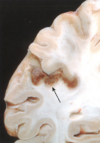

Es la acumulación excesiva de LCR en el sistema ventricular

Hidrocefalia

La mayoría de los casos de hidrocefalia están causados por alteración del flujo y de la reabsorción de LCR; la producción excesiva es una causa infrecuente asociada a los tumores del plexo coroideo.

Figura 28.2 Hidrocefalia. Ventrículos laterales dilatados observados en corte frontal a través de la región centraI del tálamo.